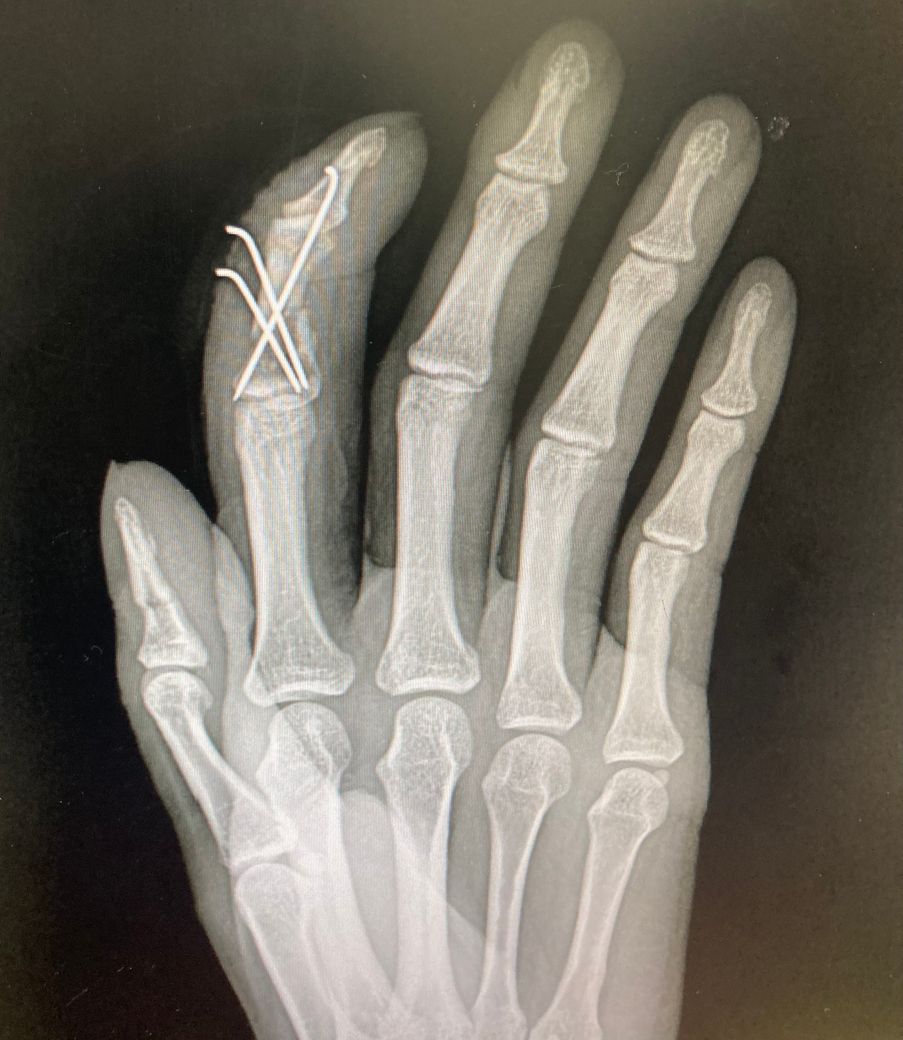

6-7주차 사진입니다 골절 부위가 좀 멀어보이

는데 유합되고있는지 될수있는지

문의드립니다

• 2번 째 사진

수지골 분쇄골절로 k-wire를 하셨네요

아직까지 엑스레이 사진에는 유합소견은 보이지 않는 것 같습니다

개인차이가 있으니 너무 불안해하지 않으셔도 됩니다

벌어져 있는 부분에 골진이 나오면서 점차 차오르고 붙을 겁니다. 지금 상태에서는 회복될 때까지 기다리는 것이 좋을 것 같습니다.